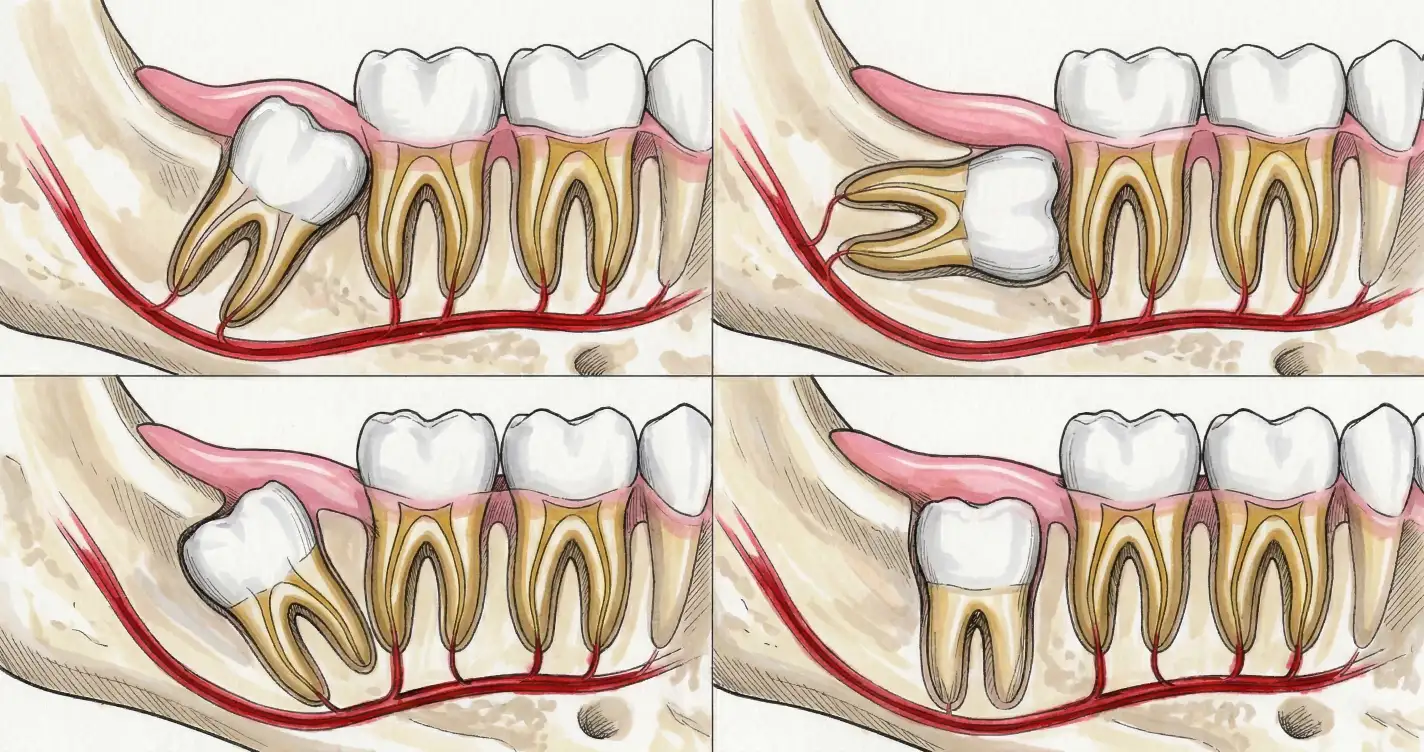

Как происходит ортодонтическое вытяжение

- Создание места. Брекет-системой освобождают пространство в зубном ряду — 3–6 месяцев.

- Хирургическое обнажение. Хирург делает разрез десны, при необходимости убирает небольшой фрагмент кости и обнажает коронку зуба. На неё приклеивается металлическая кнопка или брекет.

- Вытяжение. К кнопке подвязывается эластичная цепочка, соединённая с дугой брекет-системы. Постоянное небольшое усилие тянет зуб — миллиметр за миллиметром. Согласно систематическому обзору Mousa et al (2022), разные методы тракции (8) дают сопоставимые результаты — важнее своевременность начала. Mousa et al., 2022

- Финальное выравнивание. Когда зуб вышел в ряд, кнопку заменяют на полноценный брекет и завершают лечение стандартно.

Сроки: от 1 до 2 лет в зависимости от начального положения зуба. Процедура безболезненна.